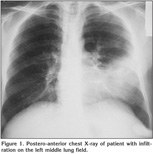

Laboratory findings were as below; erytrocyte sedimentation rate was 60 mm/hour and serum lipids were elevated [total serum cholesterol: 310 mg/dL (normal range: 140-240 mg/dL), high-density lipoprotein: 9 mg/dL (normal range: 30-85 mg/dL), low-density lipoprotein: 269 mg/dL, Very low-density lipoprotein: 33]. Pulmonary function tests revealed a restrictive pattern with FVC: 2.91 L (75% of predicted), FEV1: 2.15 L (65% of predicted) and FEV1/FVC: 74%. Carbon monoxide diffusion capacity was lower than normal; DLCO: 5.6 mmol/kPa.min (61% of predicted) and DLCO/VA: 1.2 mmol/kPa.min (74% of predicted). Arterial blood gas analysis in room air revealed pH: 7.38, PaO2: 40 mmHg, PaCO2: 42 mmHg. On the postero-anterior chest X-ray, consolidation was present in the lower zone of the left lung (Figure 1). Abdominal ultrasound revealed hepatosplenomegaly with craniocaudal length of liver and spleen 20 cm and 19 cm respectively. There was consolidation with air bronchogram at the lingula in thorax computed tomography (CT) sections (Figure 2). Three sputum samples were negative for acid-fast bacilli and tuberculosis skin test was negative. Lipid-poor diet was given to patient for hypercholesterolemia. Although non-specific antibiotic treatment of amoxicillin-clavulanic acid and clarithromycin was administered, no clinical or radiological improvement was achieved. For this reason, fiberoptic bronchoscopy was performed, which showed no endobronchial lesion. Bronchioloalveolar lavage (BAL) fluid was composed of 61% macrophages, 35% lymphocytes, and 4% neutrophiles without any cells with atypical features. After lavage procedure, an increase in oxygen saturation from 75.4% to 96.3% was detected. Cough and hemopytisis of the patient completely resolved in a few days. However, the consolidation seen on the radiographies persisted. Therefore, we performed CT guided tru-cut biopsy from consolidation area in lingular segment to exclude any malignancy. On microscopic examination of the biopsy specimen, lipid laden foamy histiocytes were seen with immunohistochemically expression of CD 68 covering the lung parenchyma (Figure 3). These findings were consistent with pulmonary involvement of SBH. Since pulmonary symptoms including hemoptysis were completely disappeared following BAL and declining of serum cholesterol levels was achieved with diet modification. No further treatment modality was planned. In his follow-up, the symptoms did not reoccur but the consolidation in the lingular segment persisted even after three years of diagnosis of pulmonary involvement.

Figure 1